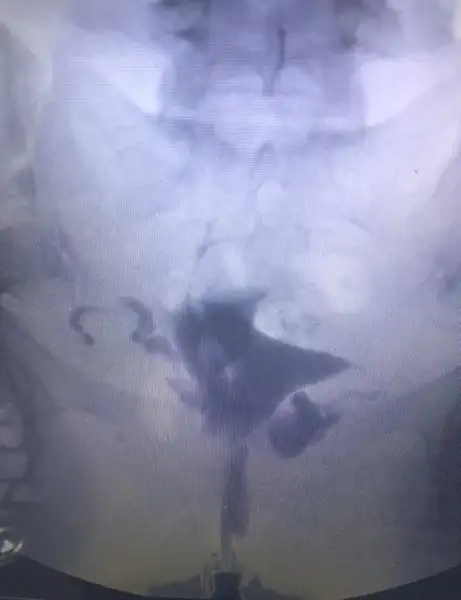

Aslında raporu alsam daha net olacak ama işte 1 haftaya çıkar ded bide acıbadem :) şişlikten bahsetmemişti doktor ama bilemedim şimdiHidroselpinks görüntüsü var gibi fotolarda ilerledikçe şişmeye başlamış sanki her iki tüpte de mevcut ama o kadar ileri düzeyde değil hidroselpinks

Şişlik dediğim fotoda ilerleyince oluşan beyaz görüntü varya sağda ve solda ondan bahsediyorum

Hidroselpinks deniliyor ona tüplerde tıkanıklık sonucu oluşan sıvının rahime sızıntı şeklinde akması iltihap yani

Ben anestezili çekildiğim için acıyı hissetmedim ama benimde gördüğüm kadarıyla ilaç iki tarafa da ulaşmış. Sizin filmde buna mı benziyrodu? İyi düşünüyorum zaten inşallah iyi de olacak sonuç :)Ben cekilirken doktor iki tarafta da aci var mi demisti. Sonra cekince baktim sizinki gibi rahmin 2 yanina ilac ulasmis kanallarin tamamen açık dedi. Ben suan sizinki icin öyle düşündüm. Açıldi demis sonuçta tıkanıklık. Iyi dusunun iyi olsun

Açık gibi gözüküyor canım bende çektirdim benim sol kapalı sağ ucundan kapalı çıktı sen be kadara çektirdin acabakızlar selamlar rahim filmi görüntülerini ekliyorum bilgisi olan yardımcı olur mu?

Aynen kapalı olanlarda baya belli oluyor. Benim ilaç gitmiş gibi görünüyor. Anestezili 800 e çekilde benimkiAçık gibi gözüküyor canım bende çektirdim benim sol kapalı sağ ucundan kapalı çıktı sen be kadara çektirdin acaba